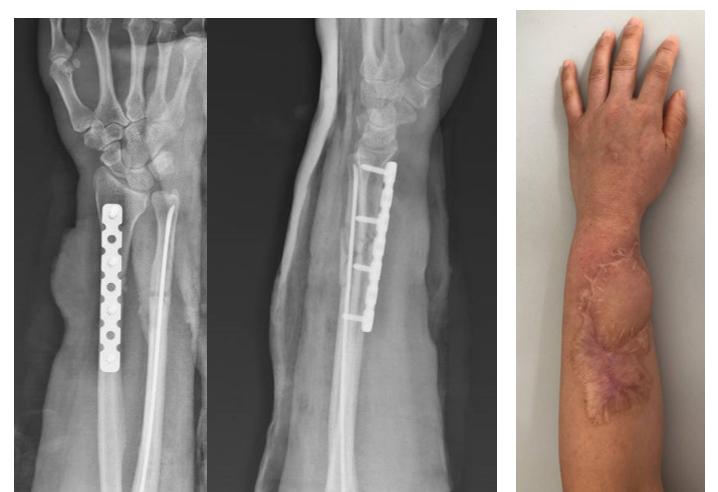

由于病人初次选择的是闭合复位的方式,创伤外科团队在仔细分析后,认为这个骨块仍然是有生物活性的。在和患者充分沟通后,在隋院长的主持下,创伤外科团队采用了生长因子注射的微创治疗方式。

(手术中定位,注射生长因子)

在C臂机的引导下定位骨不连区域,隋院长为患者注射生长因子,整个治疗过程不到5分钟时间,治疗结束后局部只有一个针眼。

大家一定很关心,这么微创的治疗方式,能不能治愈这个骨不连。这是病人手术治疗后3个月回来复查的X线片,大家可以看到骨不连的区域已经完全实现了骨性的愈合,间隙已经消失了。

(生长因子注射术后3个月)

在术后6个月的时候,在病人的要求下,取出了钢板和弹性钉。病人最后一次来医院的时候,前臂的腕关节的背伸功能、掌曲功能以及前臂的旋转功能已经完全接近正常。骨不连完全愈合,这个愈合速度其实已经超出了传统植骨手术,而且没有给病人增加额外的创伤,病人对这种治疗方式非常满意。

(生长因子注射术后6个月去除内置物)

(治疗结束的功能)